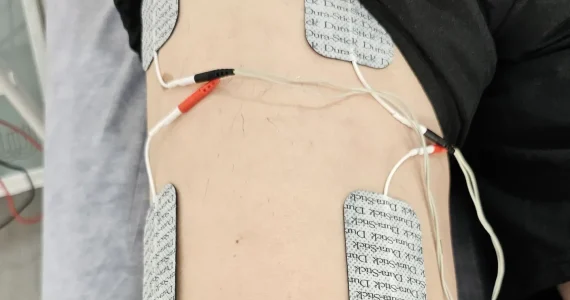

TENS

Leer más sobre TENS

La unidad TENS envía pulsos eléctricos a través de la piel para accionar la capacidad analgésica de su propio cuerpo y anular el dolor. Estos pulsos eléctricos pueden generar endorfinas y otras sustancias para detener las señales del dolor en su cerebro. TENS puede aliviar el dolor a corto plazo.